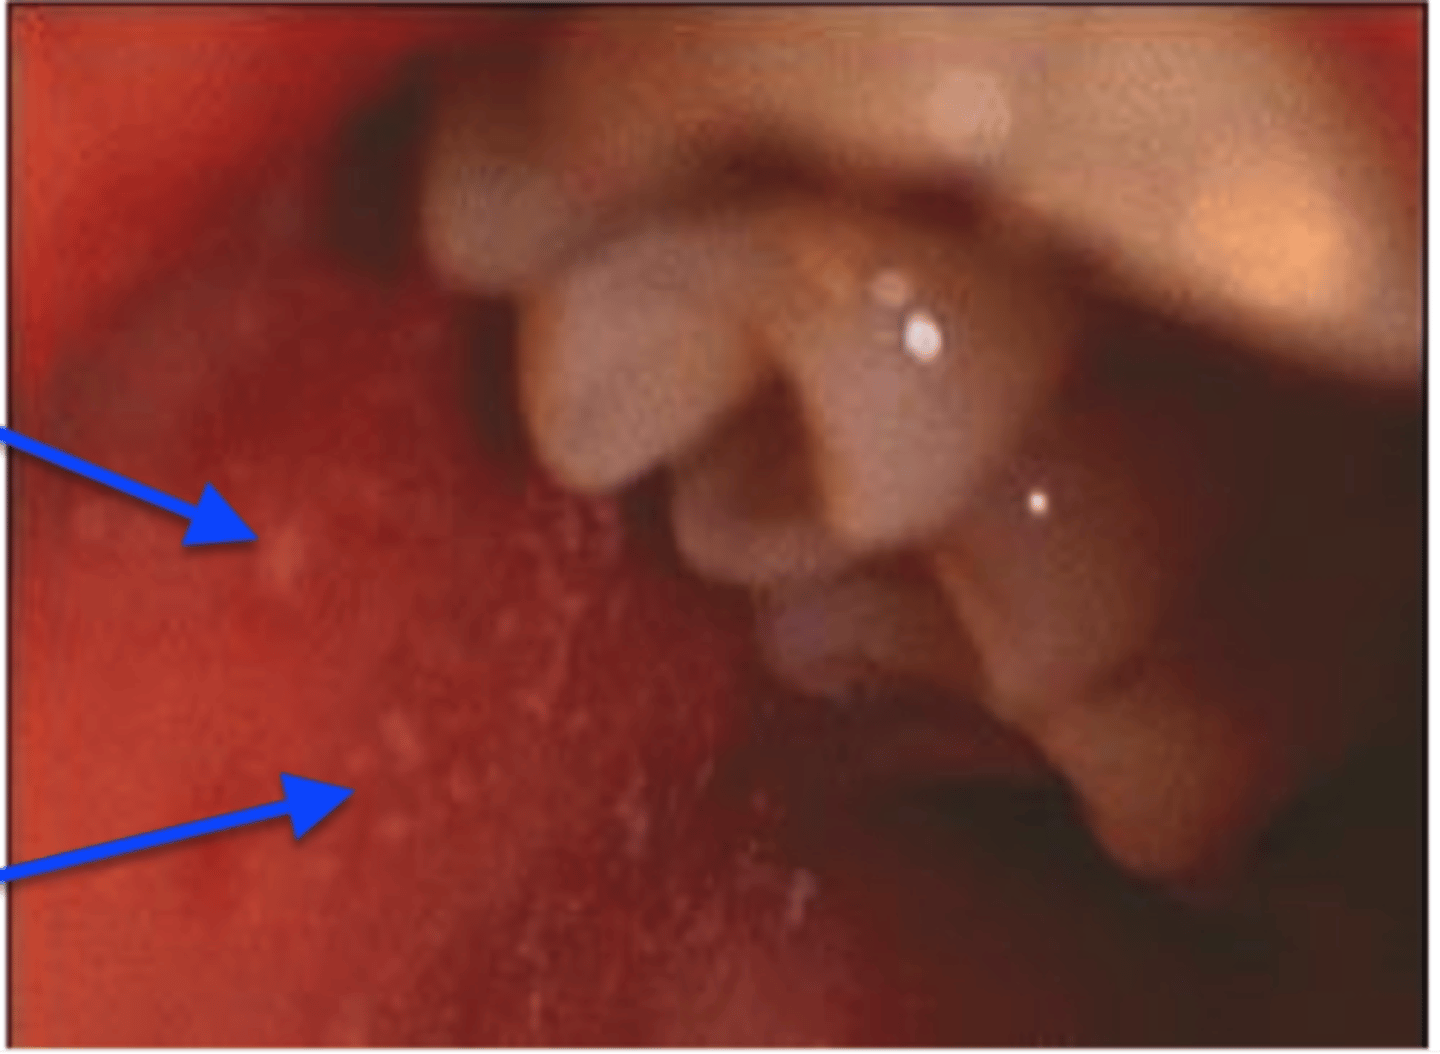

Bullous myringitis

M/C strep pneumoniae

Bullae filled with blood on TM

<p>M/C strep pneumoniae</p><p>Bullae filled with blood on TM</p>